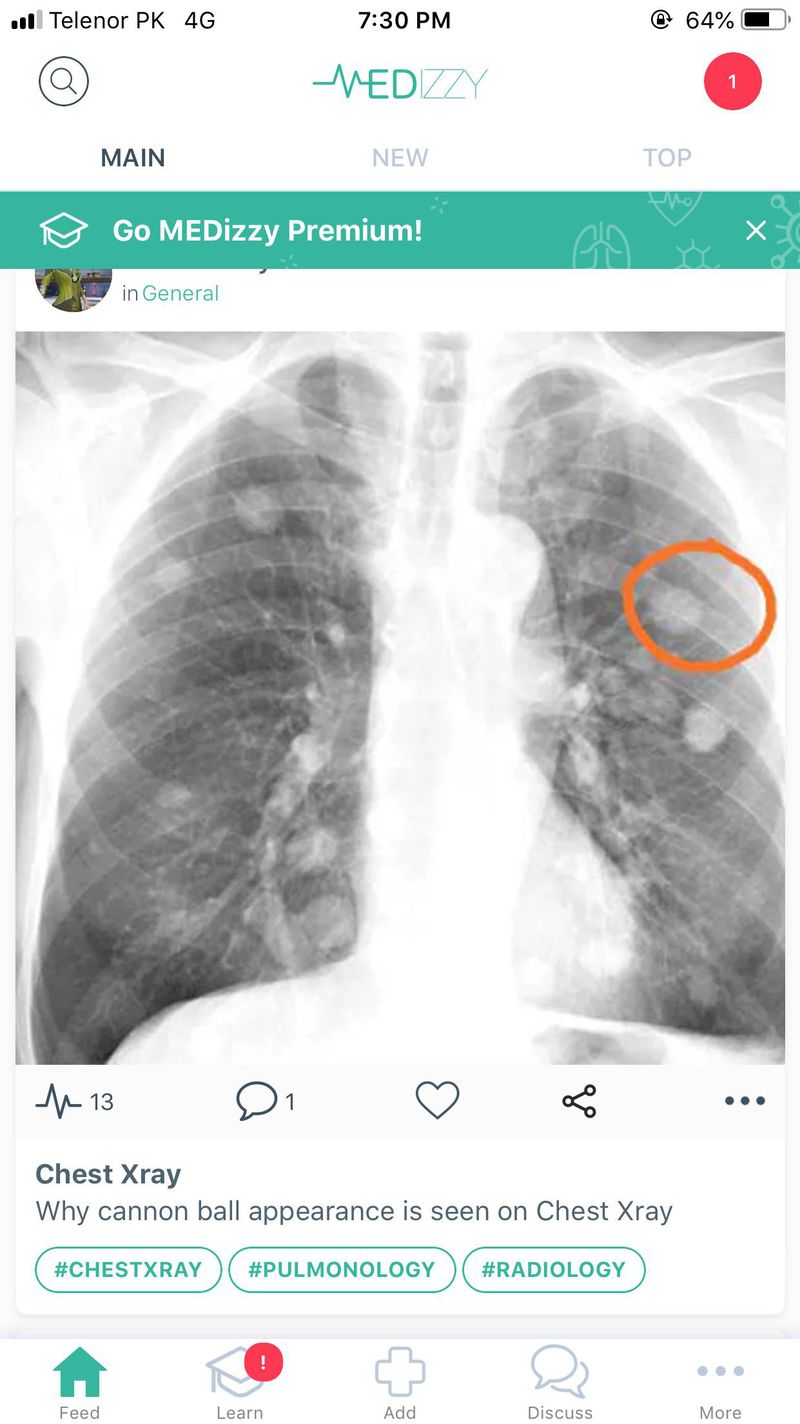

Cannon ball is appearance on X-ray

Medical X-ray